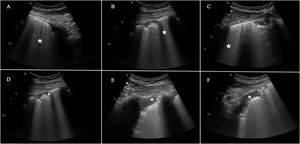

The most frequent findings in patients with acute respiratory failure.

A) Images of PLAPS, showing hypoechoic zones delimiting a poorly defined margin (small arrow) and pleural effusion (large arrow). B) Subpleural consolidation comprising a hypoechoic zone in contact with the pleural line surrounded by an irregular hyperechoic margin (shred sign). C) Air bronchogram showing hyperechoic lines (small arrow) in the context of lung hepatization, surrounded by adjacent pleural effusion (large arrow). D) Bar code pattern (stratosphere sign) in M mode, corresponding to pneumothorax. E) Seashore pattern in a lung with preserved pleural sliding. F) M mode positioned (left) in the zone corresponding to the lung point (arrow, image at right). Oscillation is observed of the seashore (white arrows) and barcode patterns (yellow arrows) in relation to the inspiratory and expiratory phases. G) Thrombus in the internal jugular vein, manifesting as a hyperechoic image occupying most of the vascular lumen. H) Pulmonary infarction: hypoechoic zone, containing a hyperechoic image (obtained with a low-frequency probe), corresponding to the bronchial tree. I) Pulmonary infarction zone (red arrow) in the lung computed tomography scan of the same patient.

The sensitivity of ultrasound in detecting pneumothorax is greater than that of conventional radiological and similar to that of CT.3,4

The ultrasound exploration of pneumothorax yields the following findings:

Change in the normal pattern in M mode from the “seashore” pattern to the “barcode” or “stratosphere” sign. A series of parallel lines of variable thickness are observed (Fig. 2). This sign may also appear on exploring large bullae that can be confused with pneumothorax.

Presence of the so-called lung point, which is seen when pneumothorax is not massive. This sign is characterized by the appearance of lung in 2D imaging in inspiration, with disappearance in expiration - corresponding to the point where the visceral and parietal pleural layers separate from each other. It can also be found as changes in M mode, consisting of a transition from the “seashore” pattern to a “barcode” pattern in successive respiratory cycles (Fig. 2 and video 1 of the electronic supplementary material [ESM]). Its specificity in diagnosing pneumothorax is 100%.

PneumoniaThe ultrasound diagnosis of pneumonia is based on identification of the B', A/B and C patterns. The presence of PLAPS adds diagnostic precision. It is very important to find subpleural condensations in the anterior lung fields, characterized by hypoechoic zones in contact with the pleural line.5 These hypoechoic zones present irregular margins, referred to as the fractal or shred sign (Fig. 2).

The appearance of a mobile or dynamic air bronchogram points to the diagnosis of pneumonia. This consists of linear hypoechoic images, sometimes with a ramified appearance, that displace with breathing if the corresponding airway is patent. The image is produced by gas penetration into the bronchial tree containing secretions (Fig. 2 and video 2 ESM).

Pulmonary thromboembolismIn the context of a patient with respiratory failure, the bilateral A pattern of the BLUE protocol implies a possible diagnosis of pulmonary embolism This exploration is complemented by vascular evaluation in search of venous thrombosis (Fig. 2) and cardiac exploration in search of signs of dysfunction or dilatation of the right ventricle.

Another possible ultrasound finding related to pulmonary embolism is the image of lung infarction, characterized by a hypoechoic, triangular subpleural zone6 (Fig. 2).